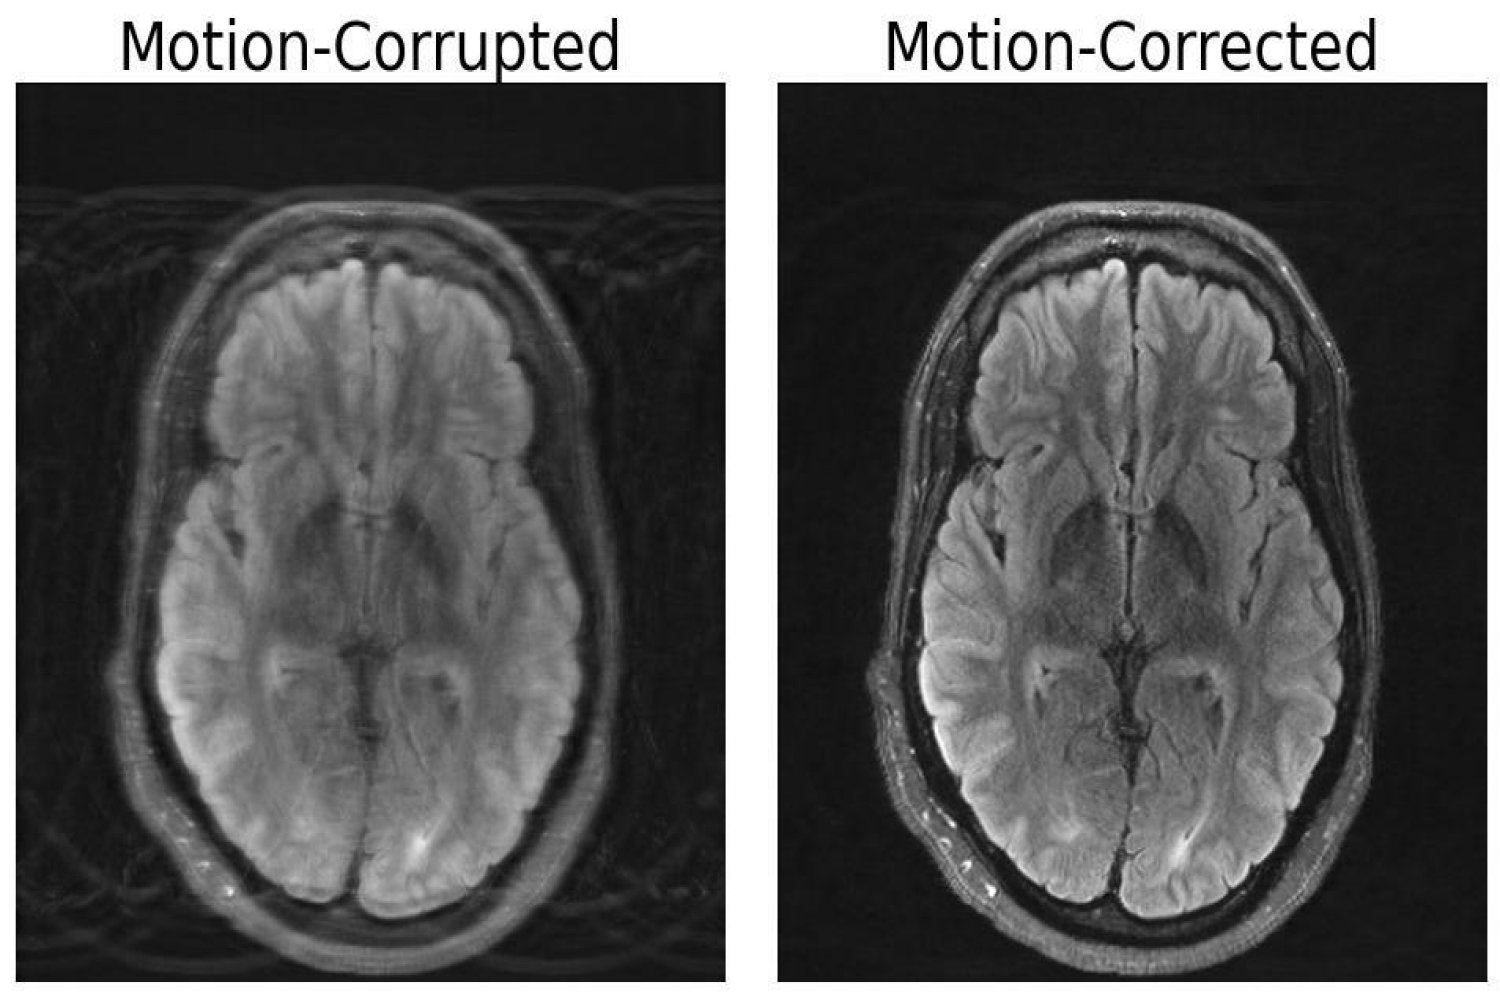

Compared to other imaging modalities like X-rays or CT scans, MRI scans provide high-quality soft tissue contrast. Unfortunately, MRI is highly sensitive to motion, with even the smallest of movements resulting in image artifacts. These artifacts put patients at risk of misdiagnoses or inappropriate treatment when critical details are obscured from the physician. But researchers at MIT may have developed a deep learning model capable of motion correction in brain MRI. “Motion is a common problem in MRI,” explains Nalini Singh, an Abdul Latif Jameel Clinic for Machine Learning in…